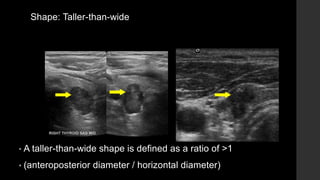

Shape: Taller-than-wide

• A taller-than-wide shape is defined as a ratio of >1

• (anteroposterior diameter / horizontal diameter)